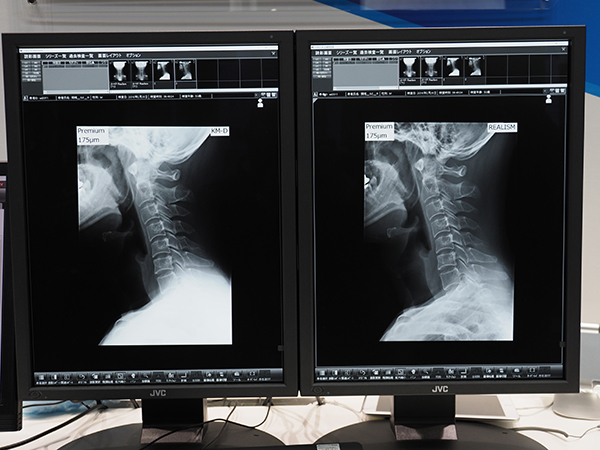

このほか,ブース内では,ワイヤレスFPDの「AeroDR fine」や適用部位を拡大した個別最適化の画像処理技術“REALISM tune”,乳がん検診ワークフロー「CADnavi」,内視鏡レポートに対応した「Unitea α」,IPネットワークカメラシステムなど医療安全に寄与する製品が展示された。

“REALISM tune”による画像の最適化処理(右)